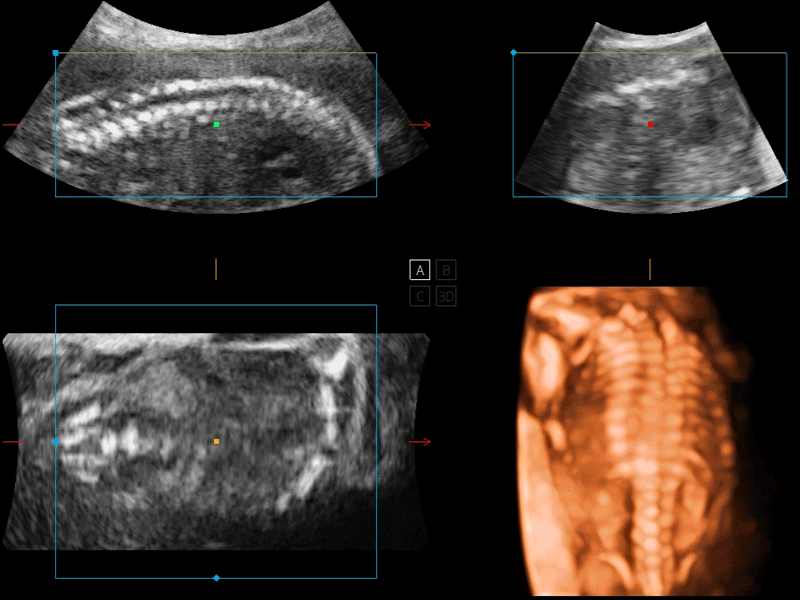

容积探头

凭借开立医疗先进的成像技术和优异的探头技术提供的清晰的图像表现,您可以更自信地做出临床决策。